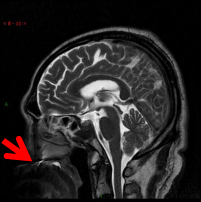

由于种植牙已固定在牙槽骨上或黏合在相应的连接物上,具有很高的牢固度,通常在3.0T(含) 以下场强的MRI设备中不会发生移动和变形,所以不用担心你的牙齿会被吸飞了哦,但在牙科植入物所在的部位可能会出现一些伪影。 像下图这样:

但是如有可拆卸的假牙或者金属牙箍,建议MRI检查时取下,不然影像可能会和下面图像一样,黑乎乎的一片,什么都看不见,这种情况就要影响诊断了。